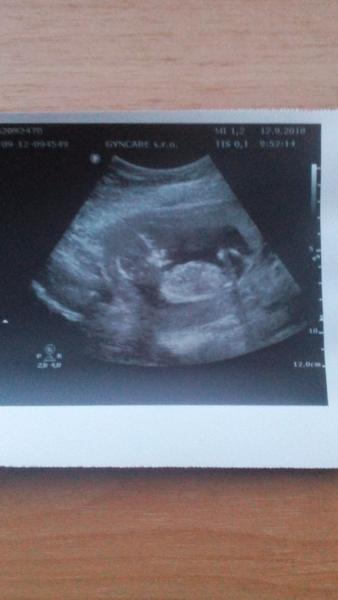

Termín porodu březen 2019

Komu taky vychází termín porodu na březen 2019? 🙂